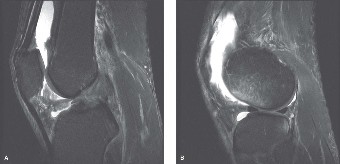

An MRI of the injured knee shows a characteristic pattern of bony edema following this injury. Where would you typically see the bone bruising in this athlete?

The correct answer is (E). MRI of an ACL tear is shown in Figure 9–2A. The ACL rupture results in a sudden translation of the tibia anterior relative to the femur, resulting in a transchondral fracture (bone bruise) of the anterior lateral femoral condyle and the posterior lateral tibial plateau (Fig. 9–2B).

Figure 9–2 A–B